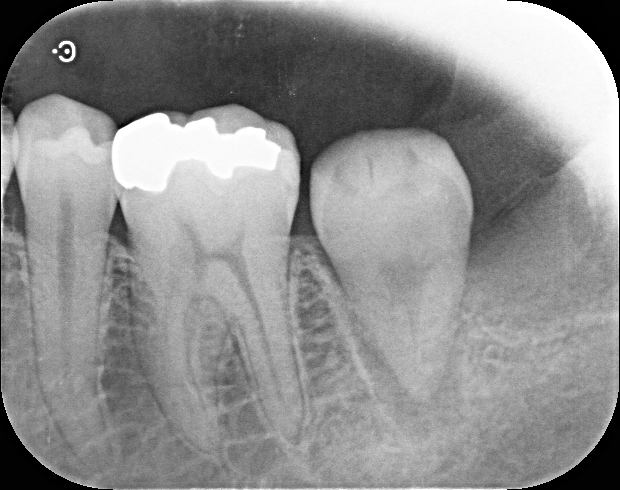

重度虫歯からのインプラント・入れ歯治療(*^-^*)

矯正治療とセラミックでの全顎治療の1例